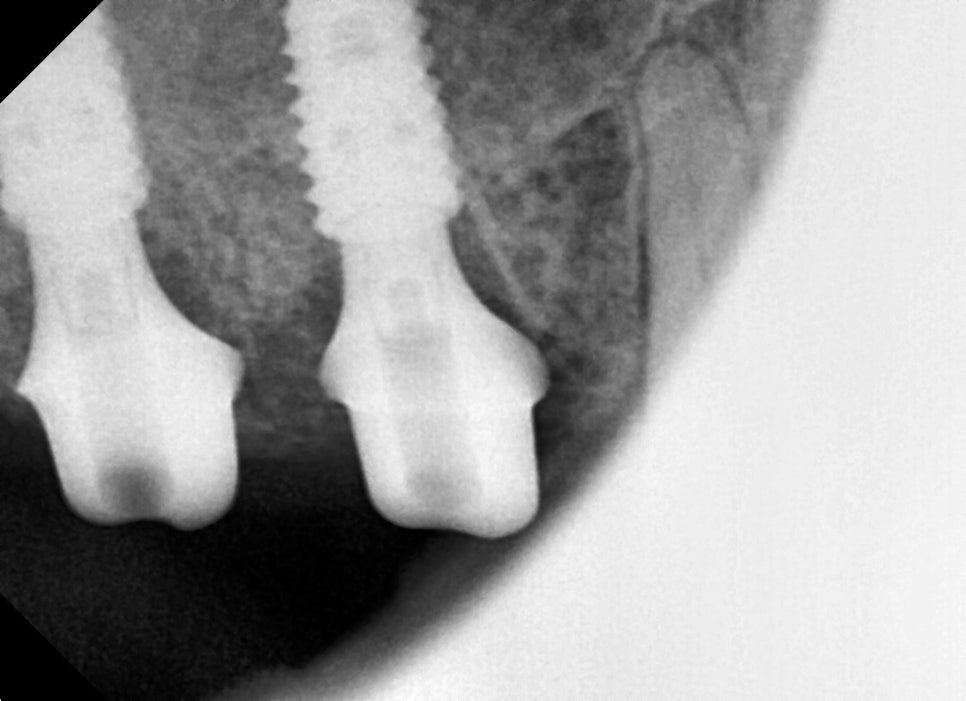

파노라마 검사와 CT 촬영을 통해

정밀 확인을 진행했습니다.

검사 결과는 단순한 충치나

크라운 파절이 아닌 치근 부위까지

금이 발생한 상태였습니다.

금이 뿌리 끝까지 뻗어 있는 경우에는

보존치료로 살리기 어렵고,

발치 후 임플란트 시술을 고려해야 합니다.

또한 위 어금니는 상악동과 가깝기 때문에,

뼈가 얇거나 염증이 심하면 뼈이식이나

상악동 거상이 함께 필요한 경우가 많습니다.